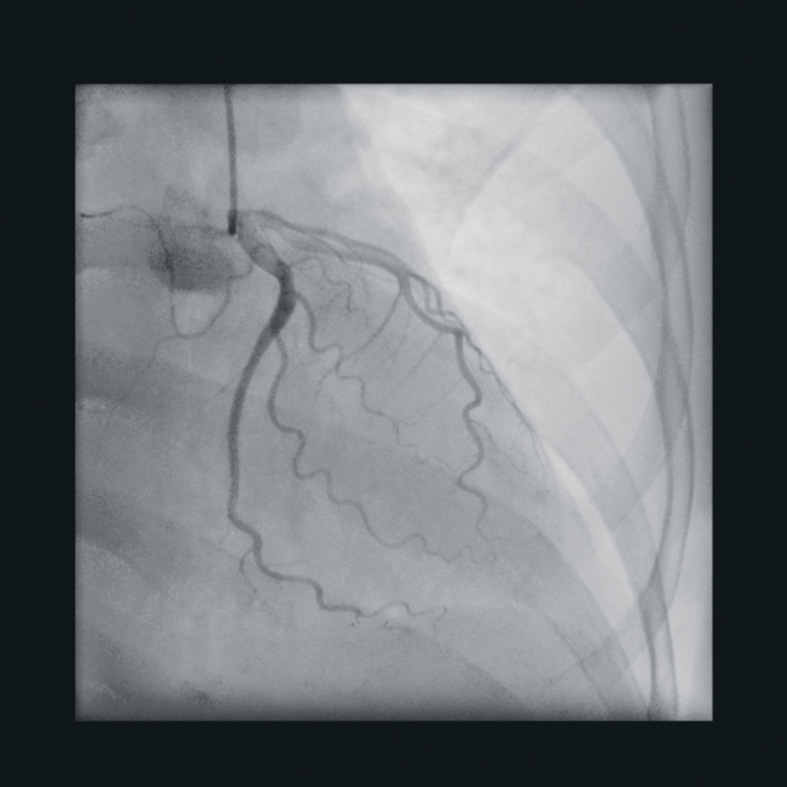

The best clinical images of the Ziehm Vision RFD Hybrid Edition